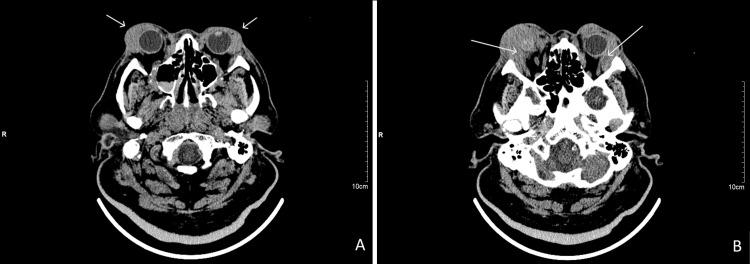

Diffuse large B-cell lymphoma (DLBCL) is the most common lymphoid malignancy in adults. It is an aggressive malignancy and requires a multidisciplinary approach with various modalities which include chemotherapy, radiotherapy as well as immunotherapy. A 63-year-old Malay male patient with underlying type 2 diabetes mellitus, hypertension, ischemic heart disease, and stage II chronic kidney disease presented with a one-month history of bilateral eye proptosis associated with lid swelling and red eye. He also complained of progressive right eye blurring of vision. Visual acuity was counting fingers on the right and 6/18 on the left. On examination, the relative afferent pupillary defect was negative. There was bilateral eye proptosis, conjunctival chemosis, and restricted extra-ocular movement in all gazes. There was also exposure keratopathy over the right eye, and intraocular pressure was raised. Bilateral cervical and axillary lymph nodes were palpable. A computerized tomography scan of the brain and orbit revealed bilateral orbital masses with no bony erosions. An incisional biopsy over the upper lid confirmed the diagnosis of diffuse large B-cell lymphoma with multiple myeloma-1 (MUM-1) positivity which defines the activated B-cell subtype (ABC). He was co-managed with a hematologist and was commenced on the rituximab-cyclophosphamide, doxorubicin, vincristine, prednisone (R-CHOP) chemotherapy regime. Bilateral eye proptosis, chemosis, and restriction of extra-ocular movement resolved after the completion of treatment. However, right eye vision remains poor as the patient developed central self-sealed corneal perforation with iris plugging which has healed with scarring. Diffuse large B-cell orbital lymphoma is a fast-growing and aggressive tumor, hence early diagnosis and prompt multi-disciplinary treatment are crucial for a good outcome.

弥漫性大B细胞淋巴瘤(DLBCL)是成人中最常见的淋巴恶性肿瘤。它是一种侵袭性恶性肿瘤,需要采用多学科方法,运用多种治疗方式,包括化疗、放疗以及免疫疗法。一名63岁的马来男性患者,患有2型糖尿病、高血压、缺血性心脏病和II期慢性肾病,出现双侧眼球突出伴眼睑肿胀和眼红1个月的病史。他还主诉右眼视力逐渐模糊。右眼视力为眼前指数,左眼视力为6/18。检查时,相对传入性瞳孔障碍为阴性。所有注视方向均存在双侧眼球突出、结膜水肿和眼球运动受限。右眼还存在暴露性角膜病变,眼压升高。双侧颈部和腋窝淋巴结可触及。脑部和眼眶的计算机断层扫描显示双侧眼眶肿块,无骨质侵蚀。上睑切开活检确诊为弥漫性大B细胞淋巴瘤,多发性骨髓瘤1(MUM-1)阳性,这定义了活化B细胞亚型(ABC)。他由血液科医生共同管理,并开始接受利妥昔单抗-环磷酰胺、多柔比星、长春新碱、泼尼松(R-CHOP)化疗方案。治疗完成后,双侧眼球突出、结膜水肿和眼球运动受限症状消失。然而,由于患者出现中央性自闭性角膜穿孔伴虹膜嵌顿,右眼视力仍然很差,穿孔已瘢痕愈合。弥漫性大B细胞眼眶淋巴瘤是一种生长迅速且侵袭性强的肿瘤,因此早期诊断和及时的多学科治疗对于取得良好疗效至关重要。